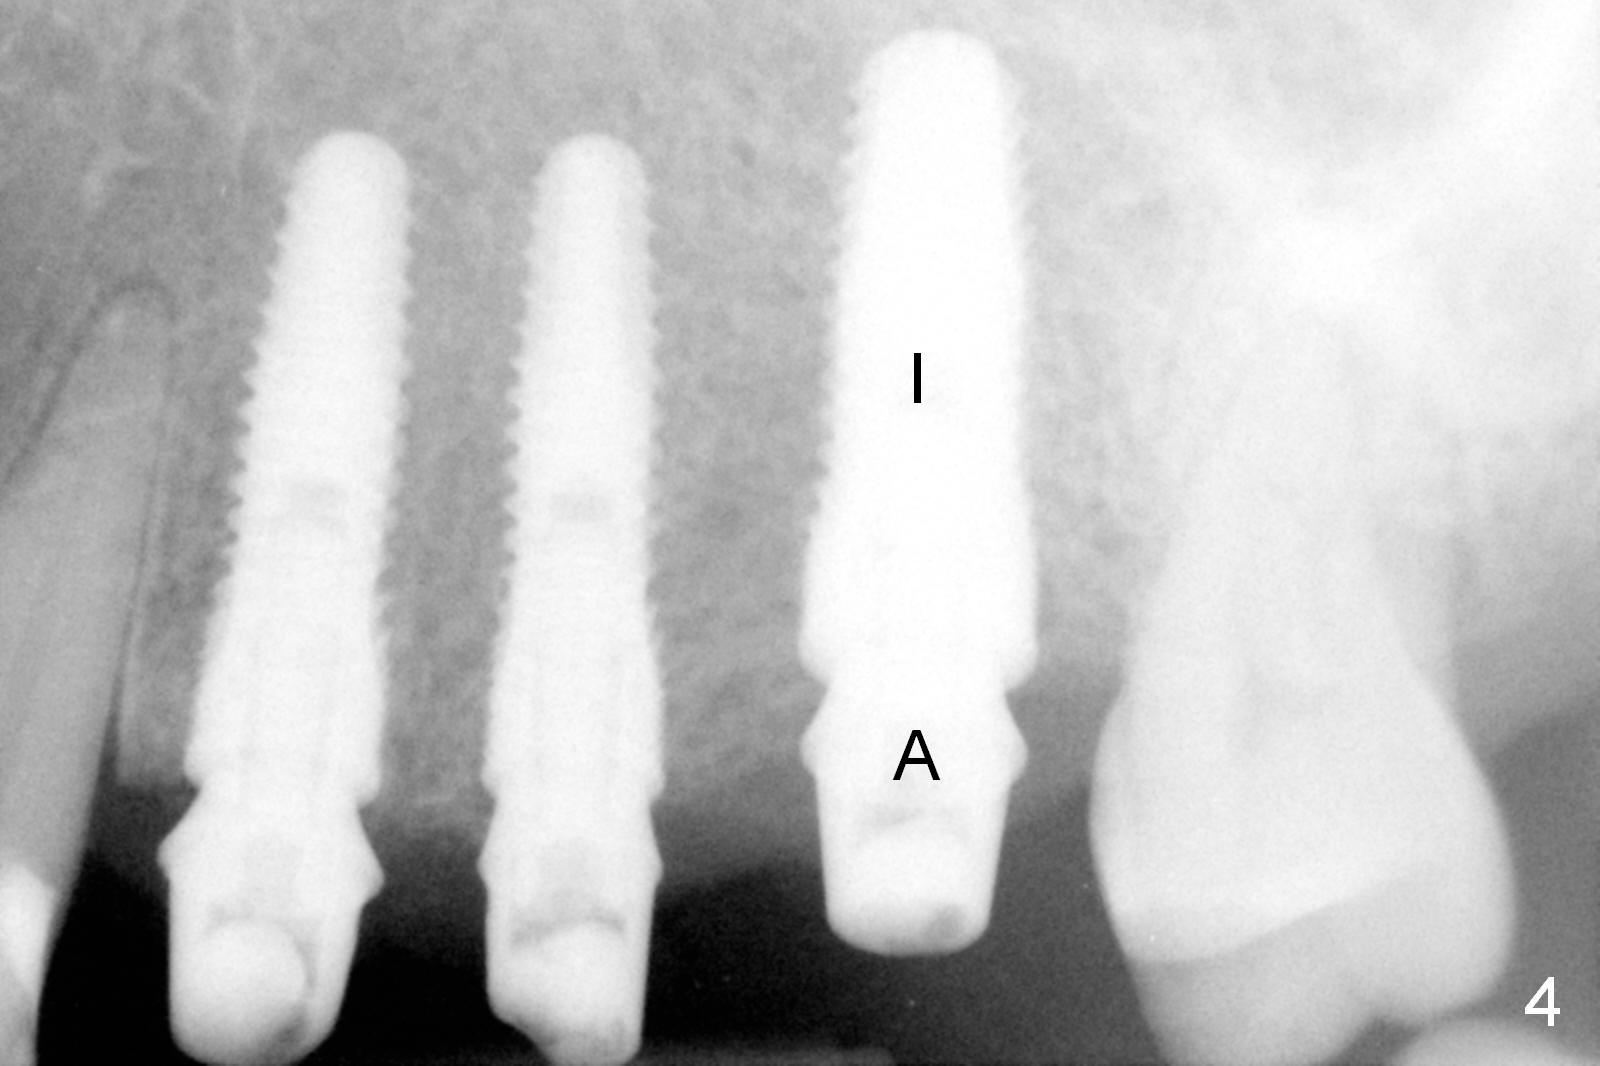

Initial osteotomies are established at the sites of #12-14 through the surgical guide (Fig.1). Following incision, the position of the osteotomies is adjusted buccopalatally where needed. Initial depth is 10 mm (Fig.2); final 14 mm. Ridge split is accomplished between the osteotomies with 7,10 and 13 mm saws from Esset Kit (Hiossen). The osteotomies are enlarged by bone expander drills from the Esset Kit RPM (Fig.3 D). When implants are placed (Fig.4 I (4.1, 3.8 and 5x14 mm)), the gap of split ridge does increase and is subsequently closed by bone graft and membrane. Definitive abutments (A) are installed to hold periodontal dressing in place securely. CBCT study reveals that the bone density between #12-14 are <200 Hounsfield units. When HU is >400, ridge split may result in bone fracture.